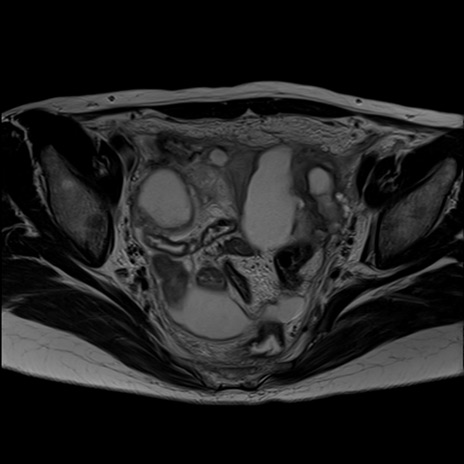

症例39 T2WI(横断像)

MRI(4日後)